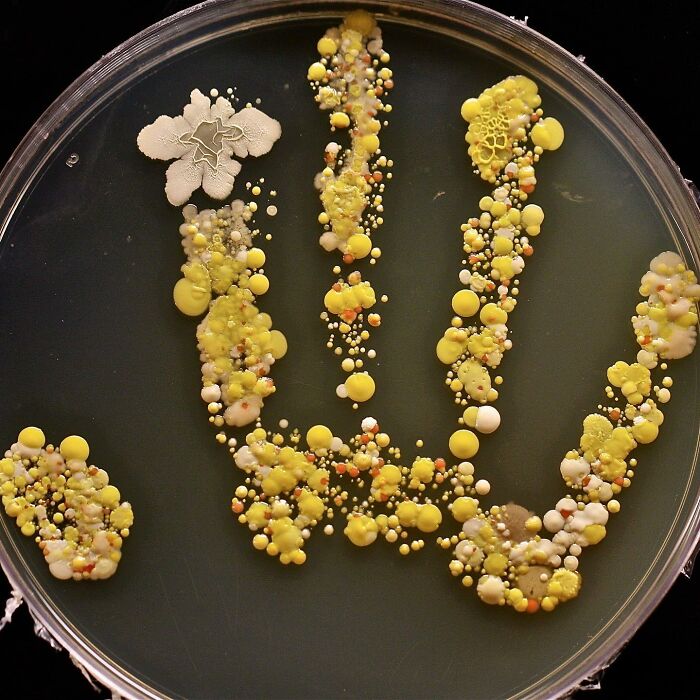

Dinner Is Served — Petri Dish With A Colony Of Bacteria On A Hand!! This Is The Handprint Of An 8-Year-Old Boy Covered In Bacteria

The boy came in from playing outside, and his mom decided to put his hand print inside a large Petri dish, incubated it for two days, and ended up with a colorful germ garden!

Consider for a moment what you've touched today. After all, our hands do all sorts of things for us – they open doors, handle money at the wet market, hold on to poles on public buses and trains, all the time while grasping our phones. They often also act as the barrier between our coughs and the rest of the world.

Up to 80% of all infections are transmitted by hands.

The colony on the hand would consist of various bacteria, potentially including both gram-positive and gram-negative species. These bacteria could belong to different genera and species, such as Staphylococcus, Streptococcus, or Escherichia coli, among others. The colony may exhibit different morphological characteristics, such as size, shape, and coloration, depending on the specific bacteria present.

Additionally, the colony might demonstrate characteristics indicative of bacterial growth, such as a visible texture or elevation. It could display features like smoothness, roughness, or irregularity. The Petri dish would provide a suitable environment for these bacteria to multiply, as it would contain a culture medium that supports their growth and sustenance.